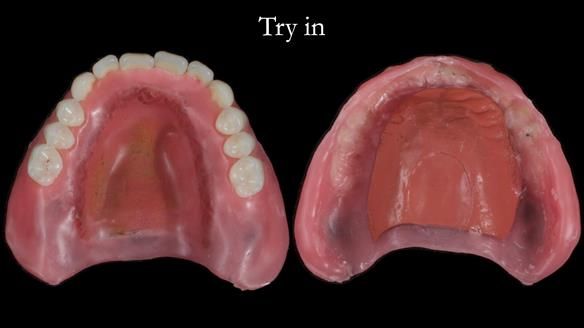

In this edition, I present the complete denture treatment for Kate, a 69-year-old American woman living in Garstang, UK. Kate had been edentulous for many years and required a set of complete dentures that closely mimicked her natural teeth. The new upper and lower dentures provided excellent retention and stability, with significant suction in the upper denture. Below, I detail the step-by-step process of her treatment, as well as my workflow for implant-supported overdentures for patients who may require them.

Treatment Process: I provided the clinical work while Rowan Garstang and Sam Hesketh delivered the technical aspects. The treatment required fifteen visits to fit and review Edgar.